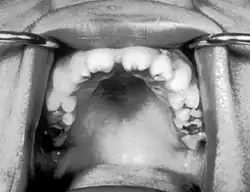

Notched incisors known as Hutchinson's teeth which are characteristic of congenital syphilis

Congenital syphilis that is diagnosed after 2 years of age, either because it was not diagnosed earlier or because it was incompletely treated, is classified as late congenital syphilis.[19] The signs of late congenital syphilis tend to reflect early damage to developing tissues that does not become apparent until years later,[20] such as Hutchinson's triad of Hutchinson's teeth (notched incisors), keratitis and deafness.[21][22]